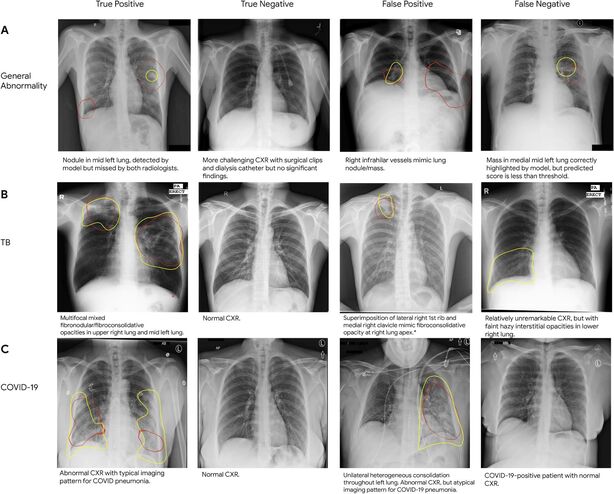

Trénování umělé inteligence nebo tzv. deep learningu pro medicínské účely není nic nového a spousta takových systémů dostala schválení příslušných úřadů pro použití v praxi. Obvykle se ale zaměřují na jeden specifický problém. Pokud ví, co mají hledat, pak jsou v tom obvykle velice rychlé a přesné. Tento systém si však volí těžší cestu a jeho úkolem je hledání jakýchkoli abnormalit, tedy odchylek od normálního nálezu.

Jako základ pro učení posloužilo 250 tisíc rentgenových snímků hrudníku, které byly doprovázeny anonymizovanými výňatky z lékařské zprávy. Aby byl vzorek pacientů co nejpestřejší, zapojily se do výzkumu krom amerických nemocnic také ty v Indii a v Číně. Prvním kolem testů pak byla identifikace plic zasažených tuberkulózou nebo koronavirem. Cílem projektu není určit konkrétní nemoc, ale pouze fakt, že je něco v nepořádku. Takové zjištění pak může poslat výše zmíněné rentgeny na začátek fronty k lidskému posouzení – o to dříve pak může být zahájena léčba.

Výsledky „práce“ umělé inteligence pak kontrolovali tři na sobě nezávislí radiologové, opět s úkolem zjistit, jestli se jedná o normální či abnormální nález. Celkem 810 snímků s 2 430 štítky pak Google uvolnil pro veřejnost, aby ji mohly použít i jiné týmy, které se zabývají strojovým čtením rentgenových snímků.